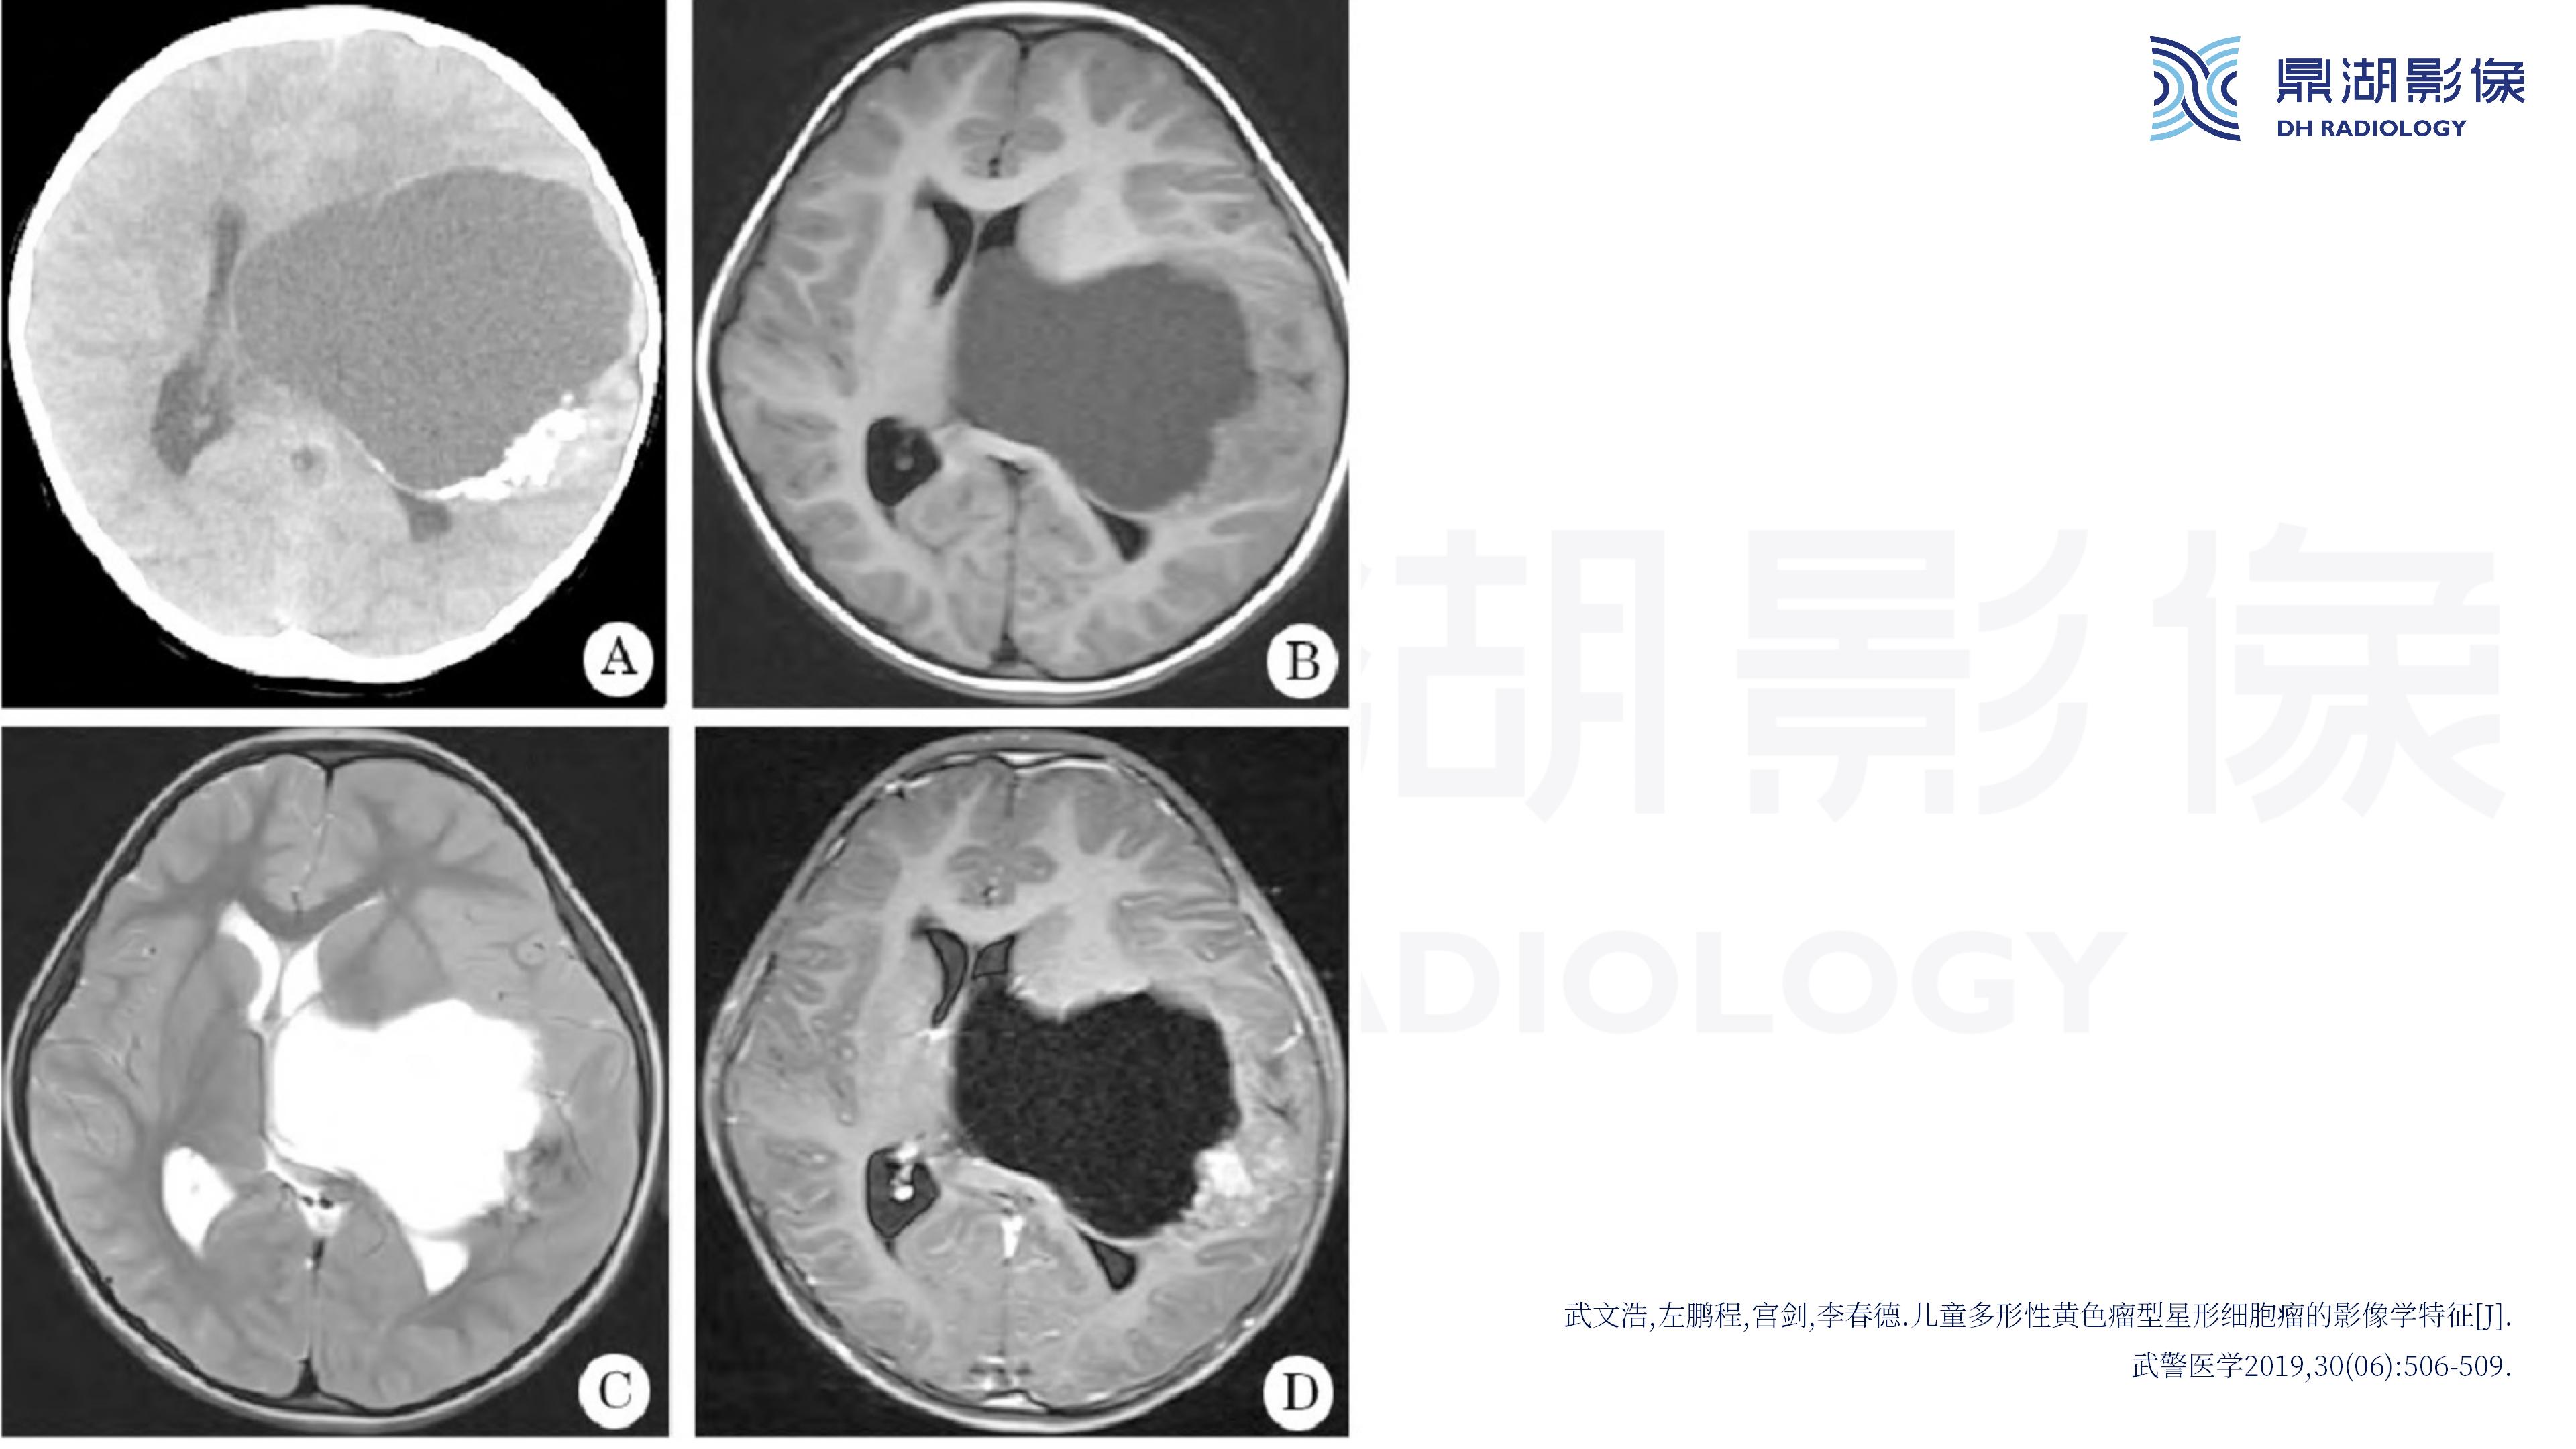

幕上毛细胞型星形细胞瘤(WHO Ⅰ级)